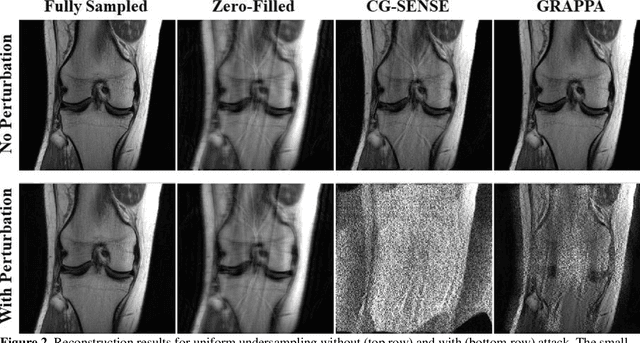

Abstract:Although deep learning (DL) has received much attention in accelerated MRI, recent studies suggest small perturbations may lead to instabilities in DL-based reconstructions, leading to concern for their clinical application. However, these works focus on single-coil acquisitions, which is not practical. We investigate instabilities caused by small adversarial attacks for multi-coil acquisitions. Our results suggest that, parallel imaging and multi-coil CS exhibit considerable instabilities against small adversarial perturbations.